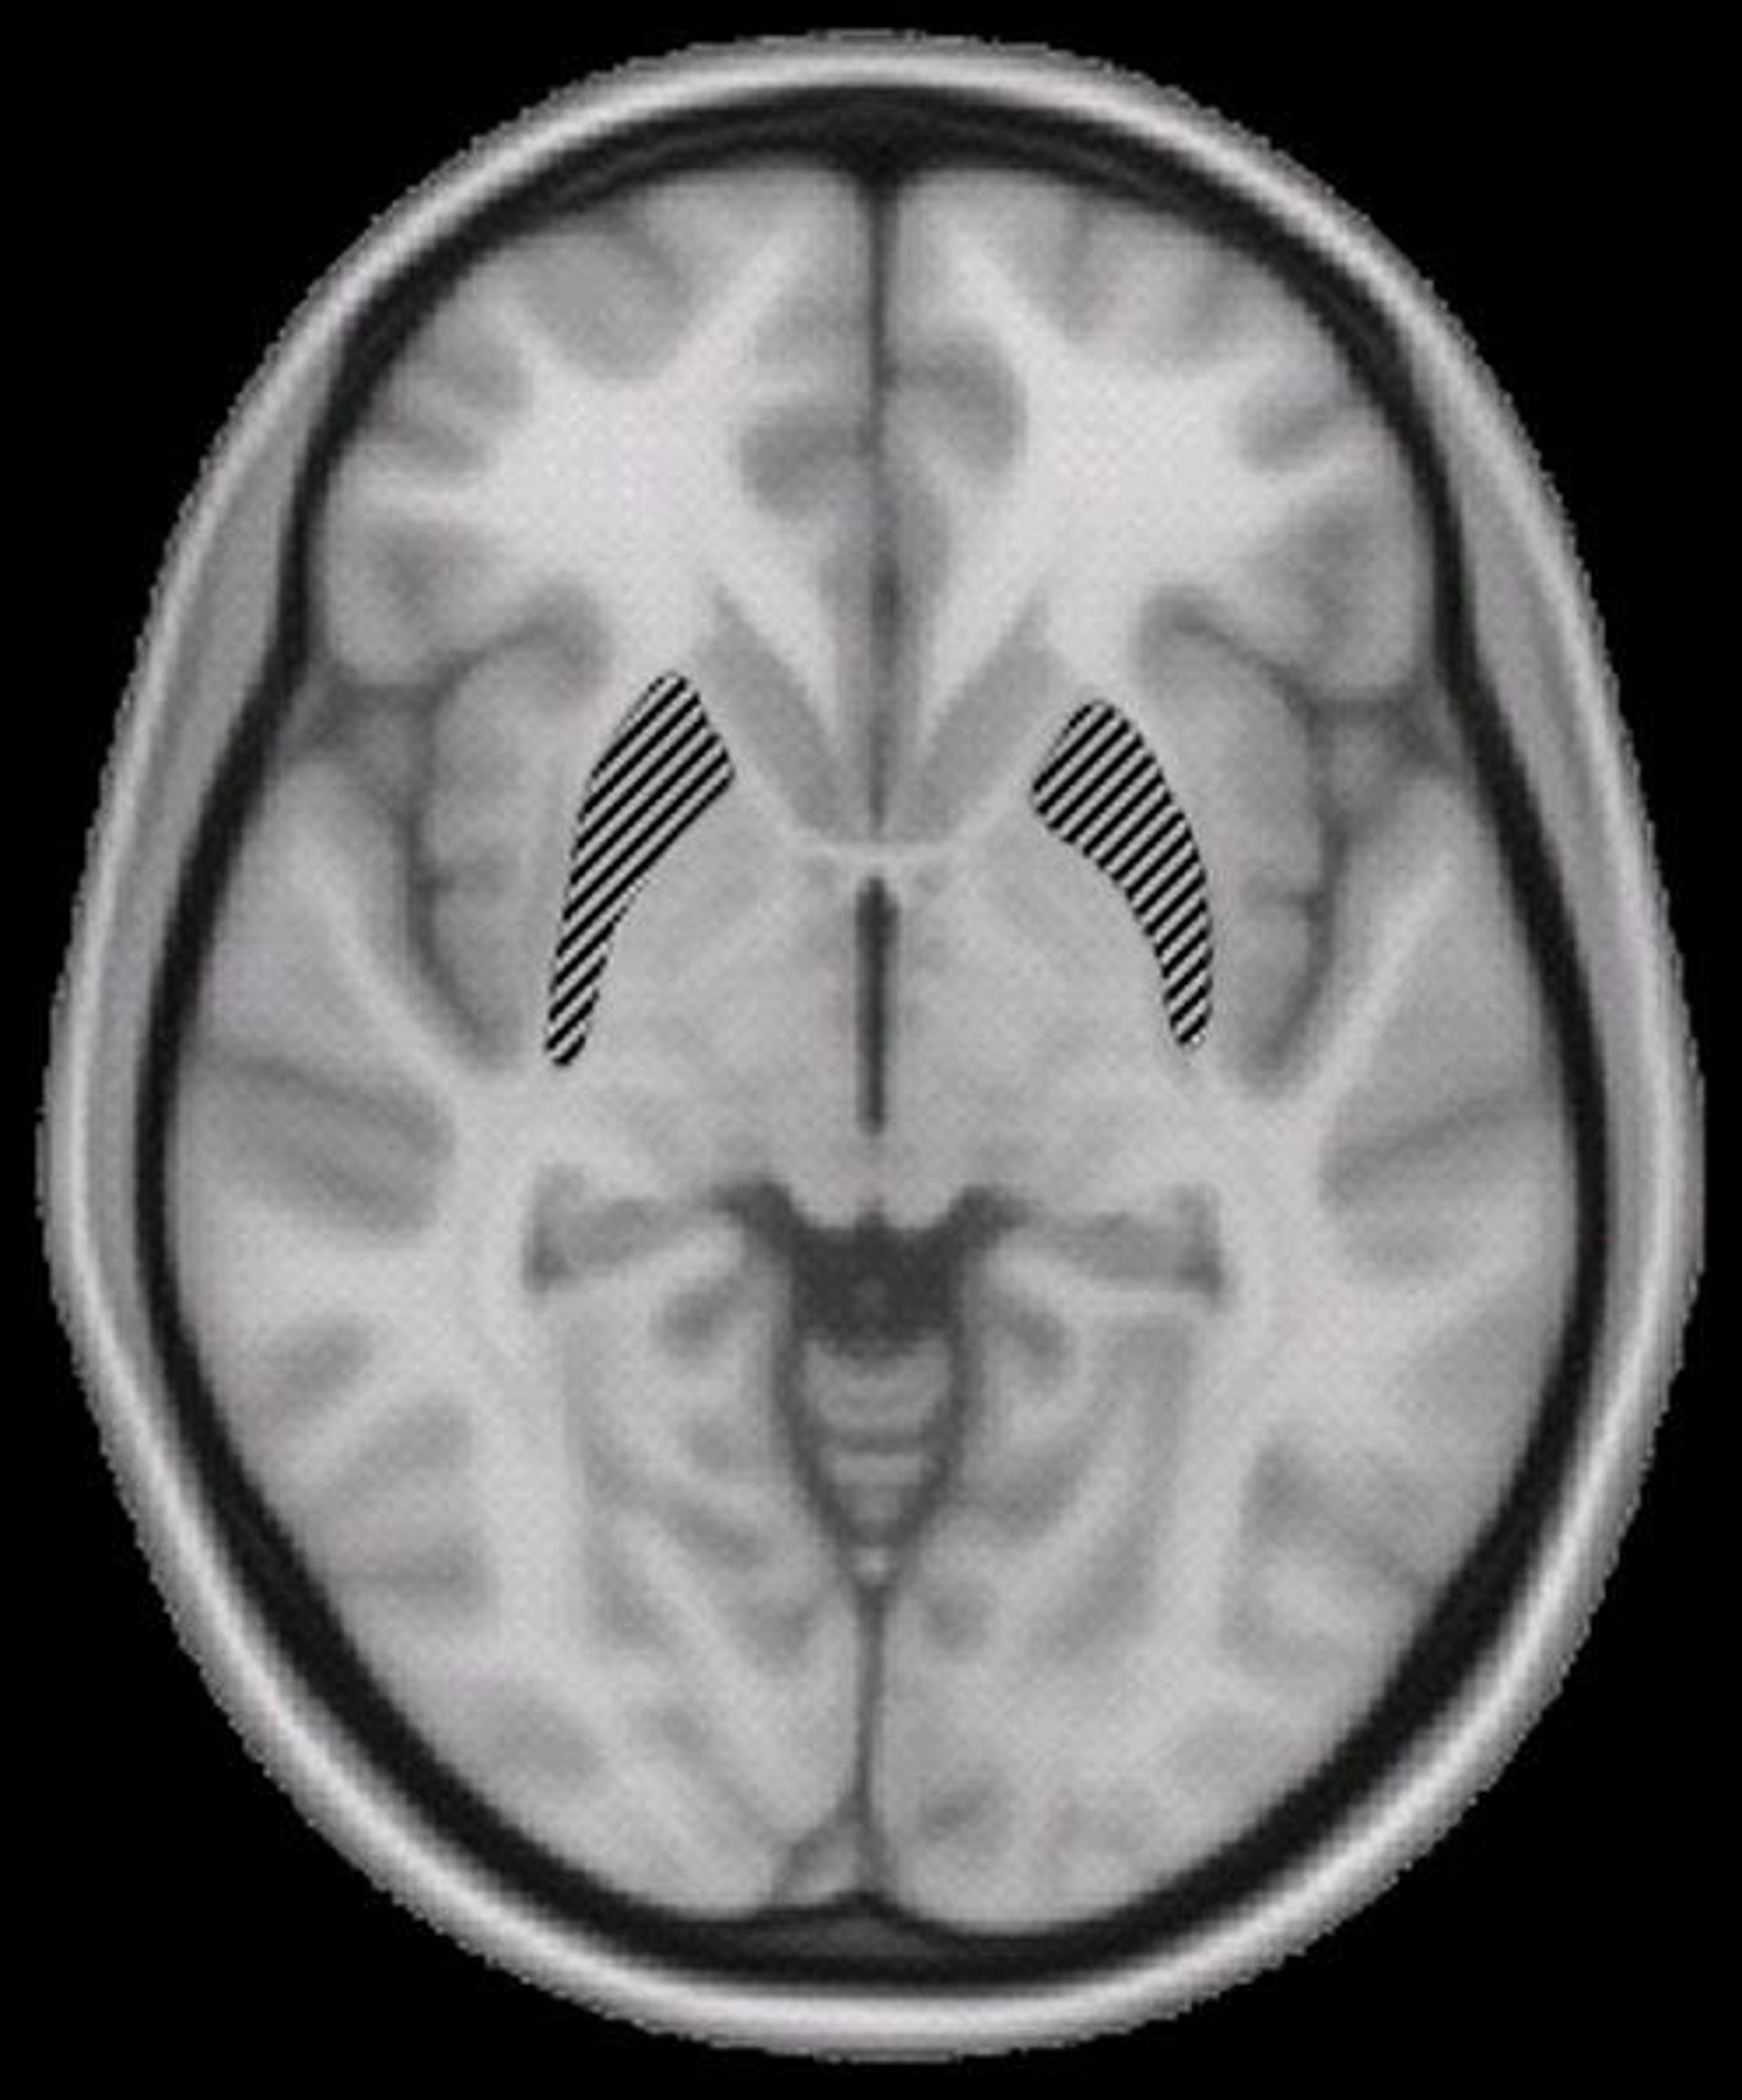

Los investigadores Sheryl Rimrodt y Laurie Cutting, de la Universidad Vanderbilt, en colaboración con la Universidad Johns Hopkins y el Instituto Kennedy Krieger, utilizaron una nueva técnica de resonancia magnética por imagen (MRI) denominada DTI-- para buscar evidencias que vincularan la dislexia con diferencias estructurales en la materia blanca situada en el hemisferio izquierdo del cerebro, donde se aloja el lenguaje.

La materia blanca se compone de fibras que actúan como los cables que permiten la comunicación entre las células cerebrales. La red del lenguaje situada en el hemisferio izquierdo del cerebro está compuesta de manojos de estas fibras y ramificaciones que se extienden desde la parte de atrás del cerebro (donde se incluyen las células de la visión) hasta las partes frontales, responsables de la articulación y el habla.

Los autores del trabajo usaron la técnica de DTI para seguir el curso de un importante bolsa de materia blanca en esta red y descubrieron que recorría la región frontal del cerebro, conocida por estar peor organizada en el cerebro disléxico. También descubrieron que las fibras en esa parte frontal estaban orientadas de forma distinta en el disléxico.